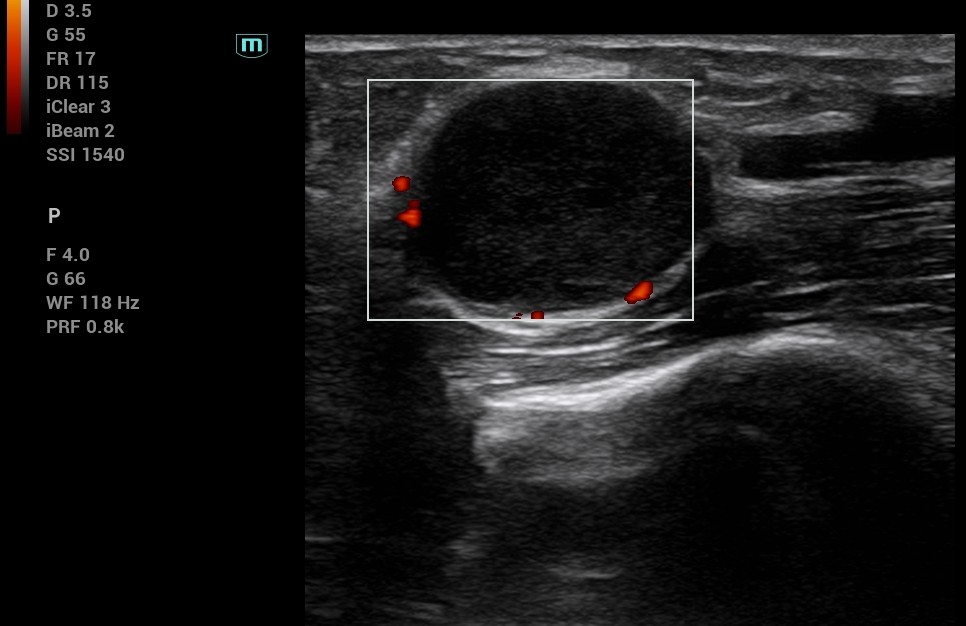

Una mujer de 67 años presentó nódulo en brazo derecho, parestesias distales y Tinel positivo. Ecografía clínica: tumor dependiente del nervio mediano. ENG y RMN confirmaron afectación nerviosa. Cirugía: schwannoma confirmado por anatomía patológica.